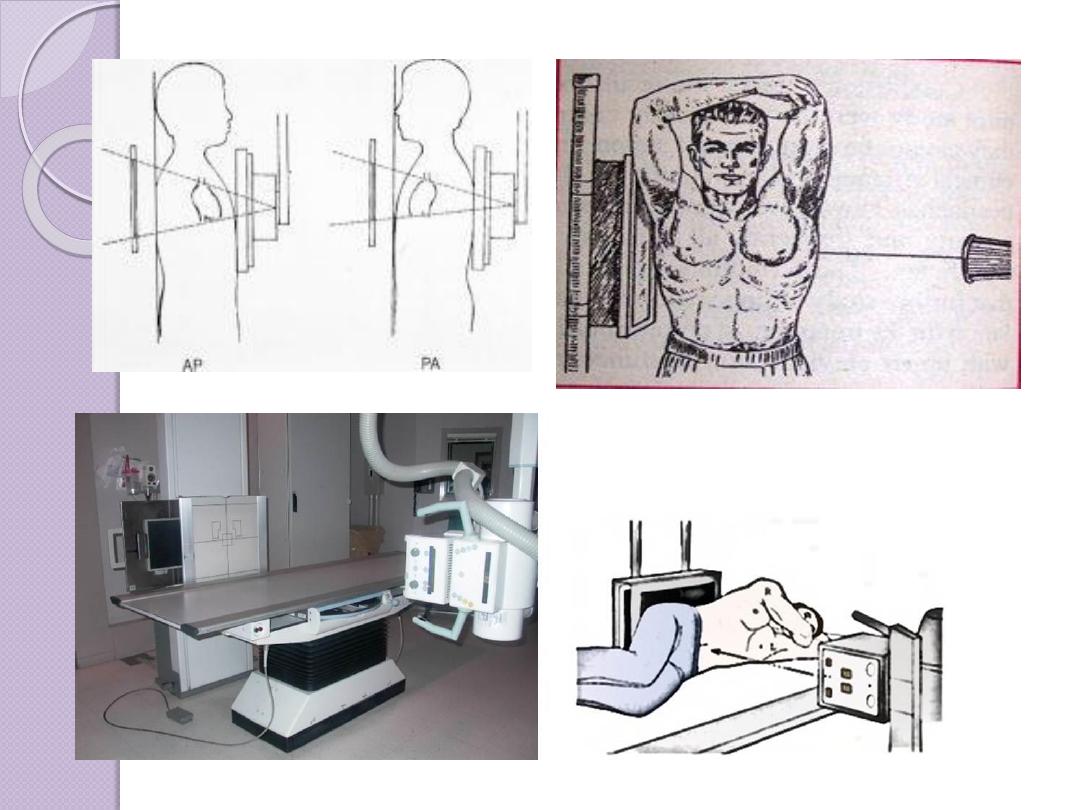

Radiographic Views

Chest and abdominal films are referred to as upright or

supine, depending on the position of the patient. In

addition, chest x-rays are usually described as

posteroanterior (PA) or anteroposterior (AP) or

lateral

These terms indicate the direction in which the x-ray

beam traversed the patient on its way to the detector.

PA means that the x-ray beam entered the posterior

aspect of the patient and exited anteriorly. AP means

that the beam direction through the patient was

anterior to posterior. A left lateral decubitus view is

one taken with the patient’s left side down.